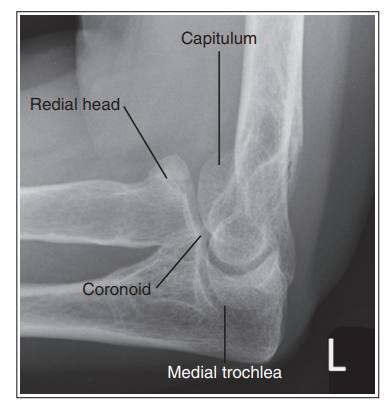

What is wrong with this external oblique elbow?

Radius and ulna are not superimposed, but coronoid can be seen

Over-rotation with obliquity of more than 45 degrees

the distal capitulum surface is demonstrated too far distal to the distal surface of the medial trochlea and the radial head is placed too far posteriorly to the coronoid process

Proximal humerus is elevated

Distal capitulum is too far proximal to the distal medial trochlear surface of the radial head is too far anterior to the coronoid process

Distal forearm is depressed